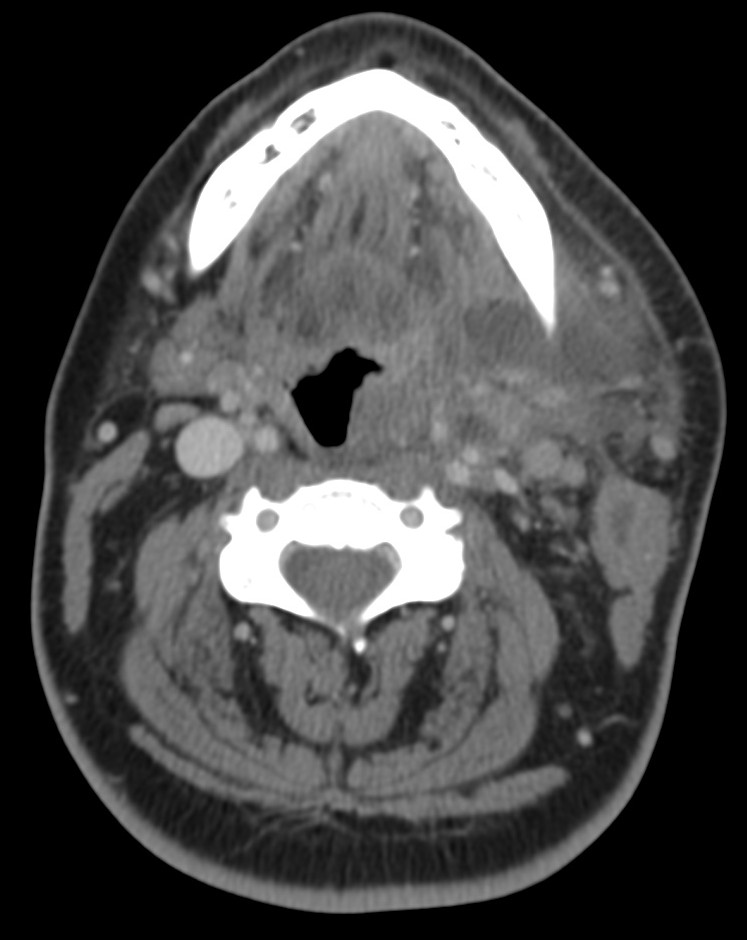

Angina de Ludwing:

No es un absceso, es una celulitis multiespacial ya que afecta al suelo de la boca y los espacios sublingual y submandibular. Se manifiesta clínicamente por dolor, hinchazón, disfagia, fiebre y elevación de la lengua, puede asociar crepitación si se deben a microrganismos anaerobios. En la TC con contraste se observa:

- Realce y edema difuso de los componentes del suelo de la boca.

- Debe determinarse si existe colección susceptible de drenaje, permeabilidad de la vía aérea y presencia de aire secundario al crecimiento de microorganismos anaerobios.

- La infección causa elevación y desplazamiento de la lengua que puede cerrar la vía aérea (debe tenerse en cuenta a la hora de manejar estos pacientes antes de realizar la prueba).